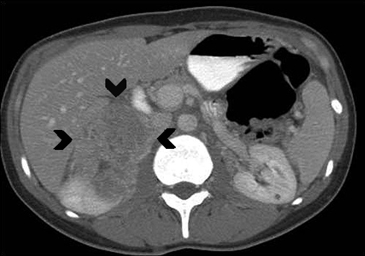

Los valores más utilizados son un 40% de lavado relativo de en fase tardía realizada a los 15 minutos y un lavado absoluto de 60%. De este modo cualquier lesión que muestre un lavado relativo mayor al 40% o absoluto mayor al 60% es consistente con un adenoma, con una sensibilidad y especificidad cercana al 100% (Figura 14 a, b y c). Dado la rapidez con que se obtiene un TAC de abdomen en la actualidad, algunos trabajos han recomendado utilizar cortes tardíos realizados a los 10 minutos, con el fin de optimizar el tiempo de examen, y utilizar un valor relativo de corte más conservador del 50%9.

A

B

C Figura 14. Tomografía computada de un adenoma suprarrenal izquierdo típico. Se ha colocado un circulo que representa la región de interés en la lesión de la glándula suprarrenal izquierda, obteniendo una medición promedio (Avg) expresada en unidades Hounsfield (UH). En fase precontraste (a) su densidad es de 0 UH, (flecha), en fase protovenosa (b) alcanza una densidad de 59 UH (cabeza de flecha), y en fase tardía (c) su lavado es de aproximadamente un 50%, llegando a una densidad de 30 UH.